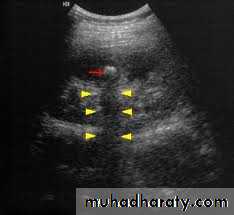

Ultrasound findings

1-Dilatation of the P.C.S. appears as multilocular fluid collection within central echo complex.-With more severe distention, dilated calyces appear as

Multiple cysts but communicating with each other unlike true cysts.

2-Stones larger than 5mm are easily seen on US but smaller ones may be missed.

-They produce intense echoes (hyperechoic) and cast acoustic shadows.

-Proximal and distal ureteric dilatation can be easily identified unlike mid-ureteric dilatation, and stones located in the middle third of the ureter are hard to be demonstrated unlike upper and lower ureteric stones (especially those lodged in the vesico-ureteric junction or pelvi -ureteric junction) which are easily identified by ultrasound.